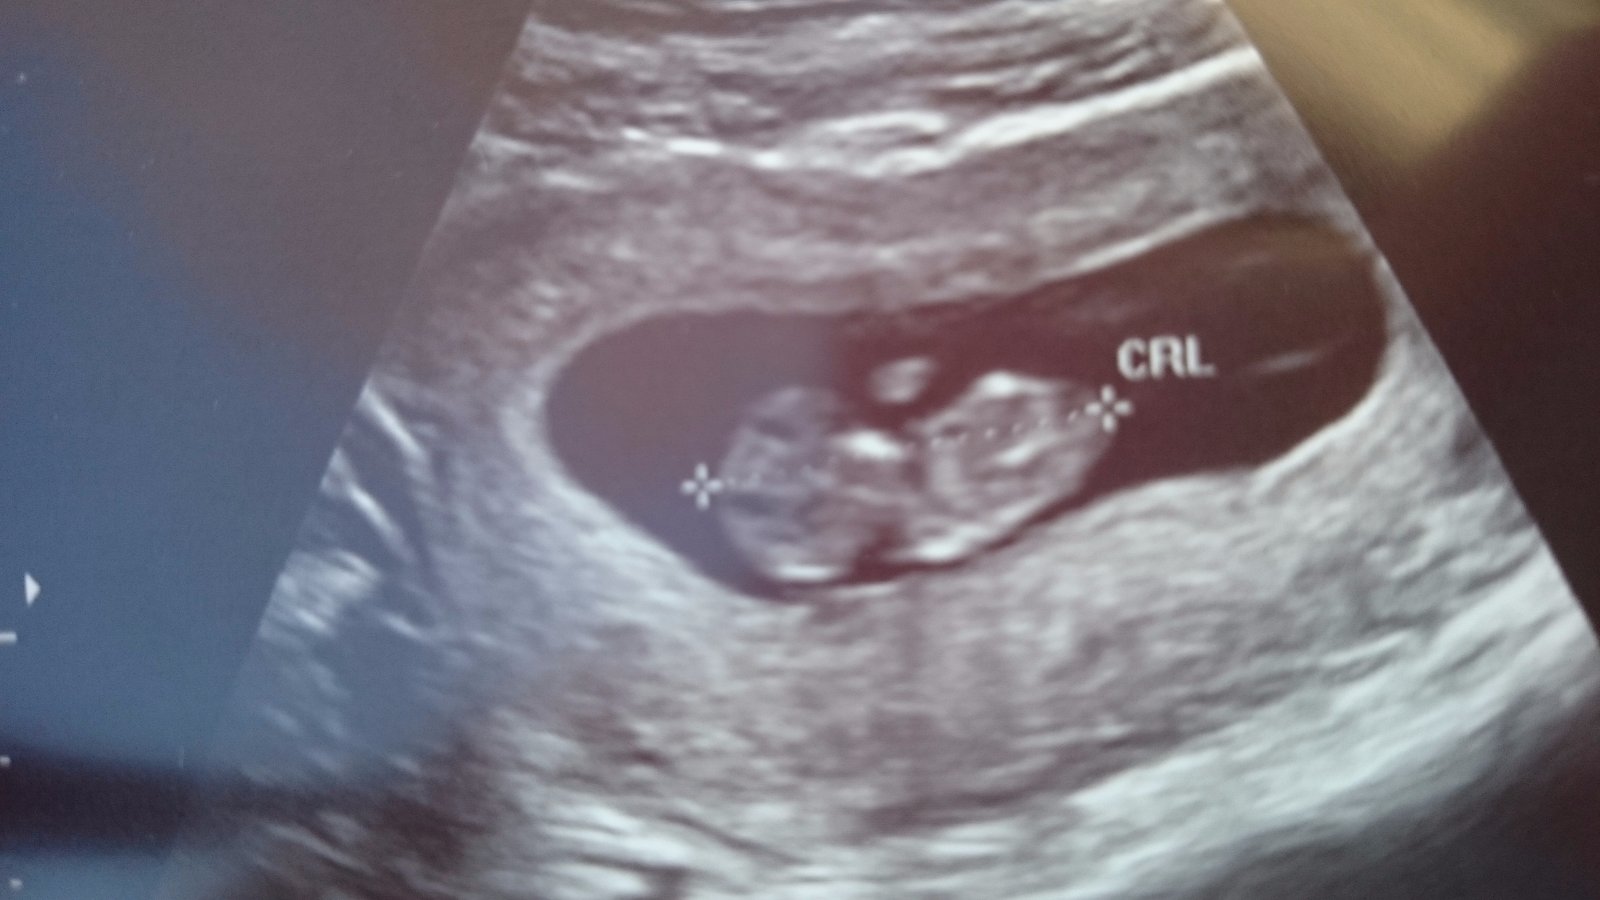

Baby,tak dnes mi mali robit velke odbery a NT,ale kedze sa potvrdilo,ze bambulo je mensie ako podla ms,tak sme to pre istotu posunuli este o 2t. Aby neboli skreslene vysledky 😄 ale dostali sme fotecku,mrvilo sa tam riadne,skvrna noje male 😊